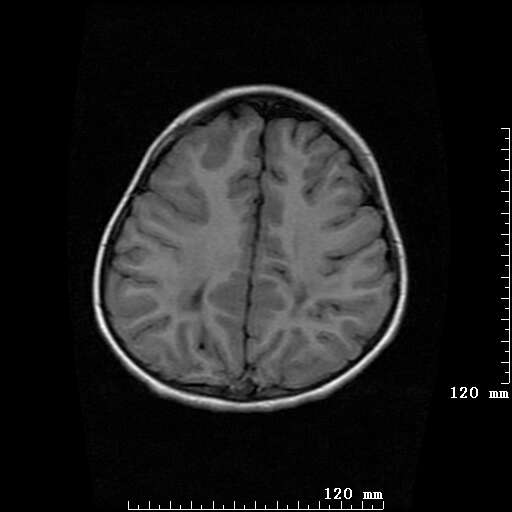

女,7岁,三岁才说话、走路。现智力尚可,走路不稳。临床怀疑大脑发育不全。

考虑 脑白质发育不良

脑折质变薄,双侧侧脑室稍扩张,支持考虑脑折质发育不良

侧脑室周围白质软化症。

考虑胼胝体发育不全,髓鞘形成不良。

支持考虑胼胝体发育不全,髓鞘形成不良。

脑裂畸形伴灰质异位

侧脑室周围白质数量减少,侧脑室不对称性扩大,左侧侧脑室后角呈方形改变,脑沟加深,结合临床考虑脑室周围白质软化症(pvl)。期待结果!

只看出灰质异位

支持脑白质发育不良。